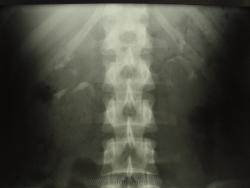

здесь говорить о расширении ЧЛС справа?

В наблюдении, похоже, имеются аберрантные внутрипочечные сосуды обеих почек; каликоэктазия (не врождённая же), больше справа, что служит основанием для дообследования больной (включая доплерографию сосудов почек...) Не факт, что гломерулонефрит единственный/правильный диагноз!..

3.Цель исследования при гломерулонефрите??? Хорошо, допустим у неё есть в почке(одной, как видно по этим снимкам) аберрантный сосуд. И что? Прожила она с ним 18 лет и ничего, а утверждать, что он(сосуд) как-то повлиял на возникновение гломерулонефрита - шаманизм.

4.Размеры ЧЛС нормальные.